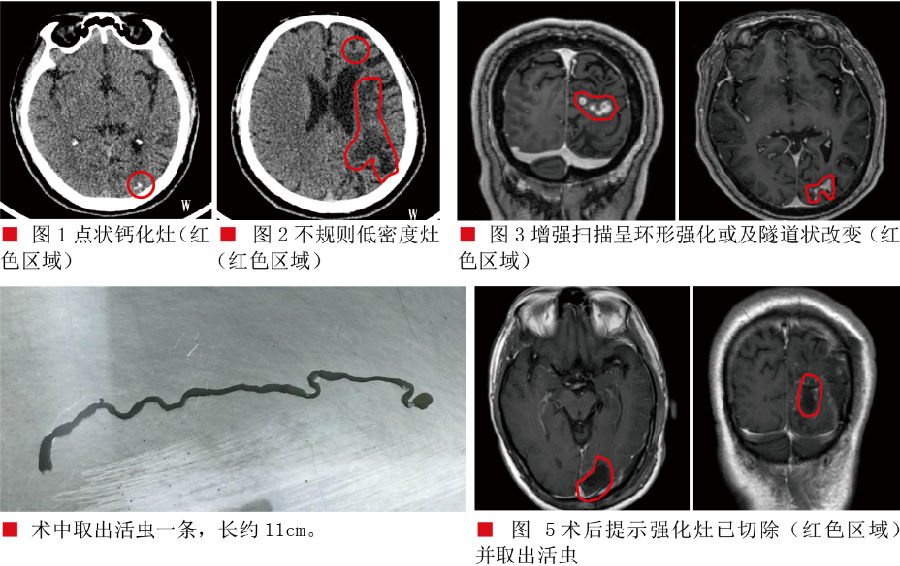

诊疗经过:入院后查头部CT示:左枕局部可见钙化影(如图1),左侧额顶枕多发软化灶(CT表现为低密度灶,如图2)。头颅MRI增强扫描显示:

1.左侧额顶枕叶及左侧基底节区多发病变,现增强后左侧枕叶病变异常强化,考虑存在寄生虫感染(脑裂头蚴病可能);

2.脑白质少许脱髓鞘灶。血/脑脊液化验示寄生虫抗体IgG/IgM:阳性。诊断为:脑裂头蚴病,继发性癫痫。排除手术禁忌症后在全麻下行左枕部开颅脑裂头蚴切除术,手术过程顺利,抓获裂头蚴活虫一只,长约11厘米。术后患者无明显功能障碍,已康复出院。

③影像学检查:CT:

CT检查有以下三联征表现:

1.白质区不规则的低密度占位灶,伴有临近脑室略微扩张;

2.点状钙化灶;

3.病灶结节状或不规则增强。

MR:影像学特征:

1.T1W1呈低信号,T2W2呈稍高或等信号,冠冠状位和矢状位增强图像呈更清楚的梭形或柱形隧道样改变;

2.聚集的小环状或串珠样强化;

3.不同阶段的病灶交替出现在同一层面的图像上;

4.病灶具有游走性。

本病的治疗关键是去除活的虫体,手术为首选方法。由于裂头蚴的活动性,往往造成多发病变,给确定活虫位置造成困难,特别是当病变累及功能区时,使得手术抓获活虫难度增加。我们的经验是:重视患者癫痫发作症状学演变和最近的影像学变化,往往新的病变区域或新的症状产生代表区域是活虫所在区域。而且神经导航指引下手术是必需的。资料显示,一般只要去除完整的虫体,病人的临床症状即可得到明显的缓解或痊愈,一般无需特殊药物治疗。